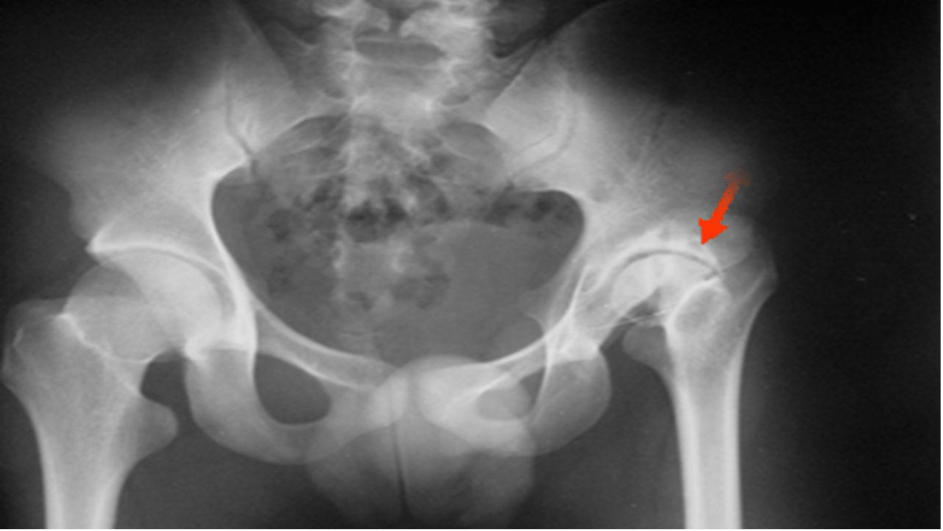

Radiograph of osteoarthritis in right hip joint with moderate loss of Moderate Arthritis In Hip Joint A hip damaged by osteoarthritis. Common symptoms of hip arthritis may include: Pain in the hip joint, which may include pain in the groin, buttock, or outer thigh. Symptoms of hip arthritis may include pain in or near the hip joint, stiffness, audible clicking sounds when moving the hip, and weakness. Hip osteoarthritis is the gradual loss of cartilage and. Moderate Arthritis In Hip Joint.